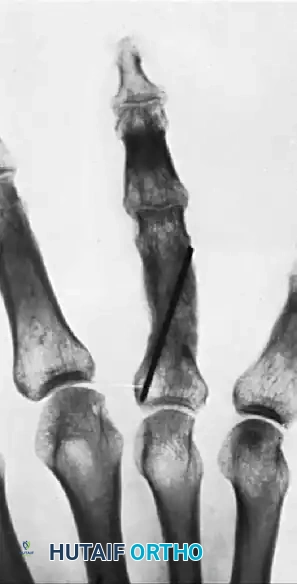

FIGURE 67-72: Malunited fracture of the fifth metacarpal neck treated by open reduction and fixation with one Kirschner wire inserted obliquely. This is rarely necessary because the normal motion of the fifth carpometacarpal joint permits tolerance of up to 40 degrees of angulation at the fracture site.